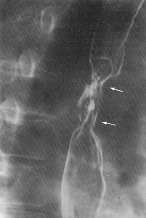

Diverticolul Zenker reprezinta o forma particulara, fiind un diverticol de pulsiune localizat īn apropierea jonctiunii faringoesofagiene la nivelul peretelui posterior.Cānd este plin, comprima si īngusteaza lumenul esofagian.

Diverticolii din 1/3 medie sunt īn majoritatea de tractiune, sunt localizati īn regiunea hilara si se formeaza prin tractiunea esofagului de catre aderentele fibroase ganglionare. Īn apropiere, se pot evidentia ganglioni hilari calcificati.

Imagistic diverticolul apare ca un plus de substanta ce iese din contur si este legat de esofag printr-un pedicol. El are o forma rotund-ovalara cānd mecanismul de formare este prin pulsiune sau triunghiulara cānd se formeaza prin tractiune. Este bine delimitat si are o structura omogena. Īn repletie, bariul poate ramāne īn punga diverticulara cāteva ore si, īmpreuna cu aerul, realizeaza un nivel hidroaeric.